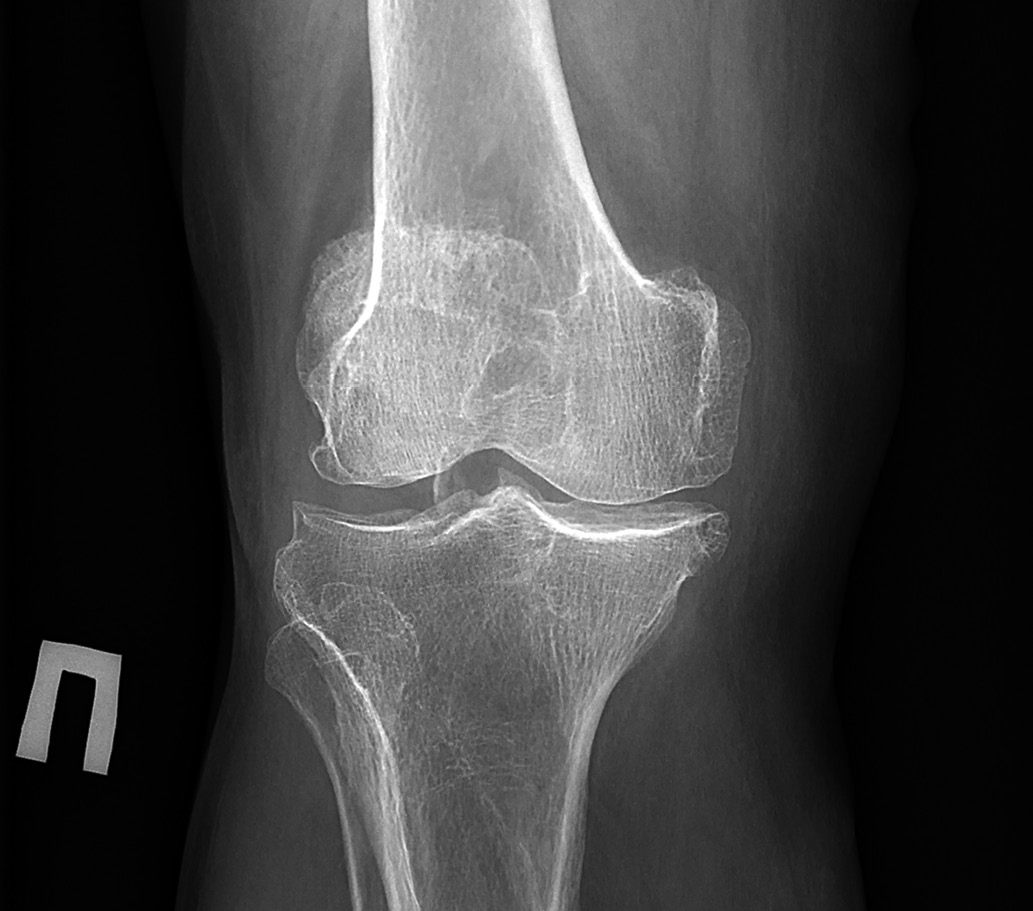

Нормальный размер суставной щели коленного сустава